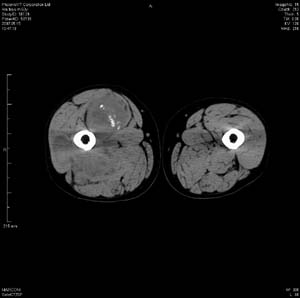

男 63岁 右大腿无痛性肿块11年,x片右大腿软组织肿块影,余无明显异常.ct值-13__239hu

右大腿股内侧股与收肌间隙间多发囊实性占位,界清.内示斑点状钙化.局部骨质无异常.肌肉推压移位表现.

考虑肌间隙病变.可有1,神经来源肿瘤.2,血管来源病变.3,淋巴来源肿瘤.4,脂肪来源肿瘤.5,滑膜来源肿瘤.结合病史只能考虑良性占位.建议增强或mri进一步分析.

同意,病史较长,病变周围分界清晰,考虑良性病变。病灶内有多发斑点状钙化,沿肌间隙生长,血管瘤或淋巴管瘤首先考虑。